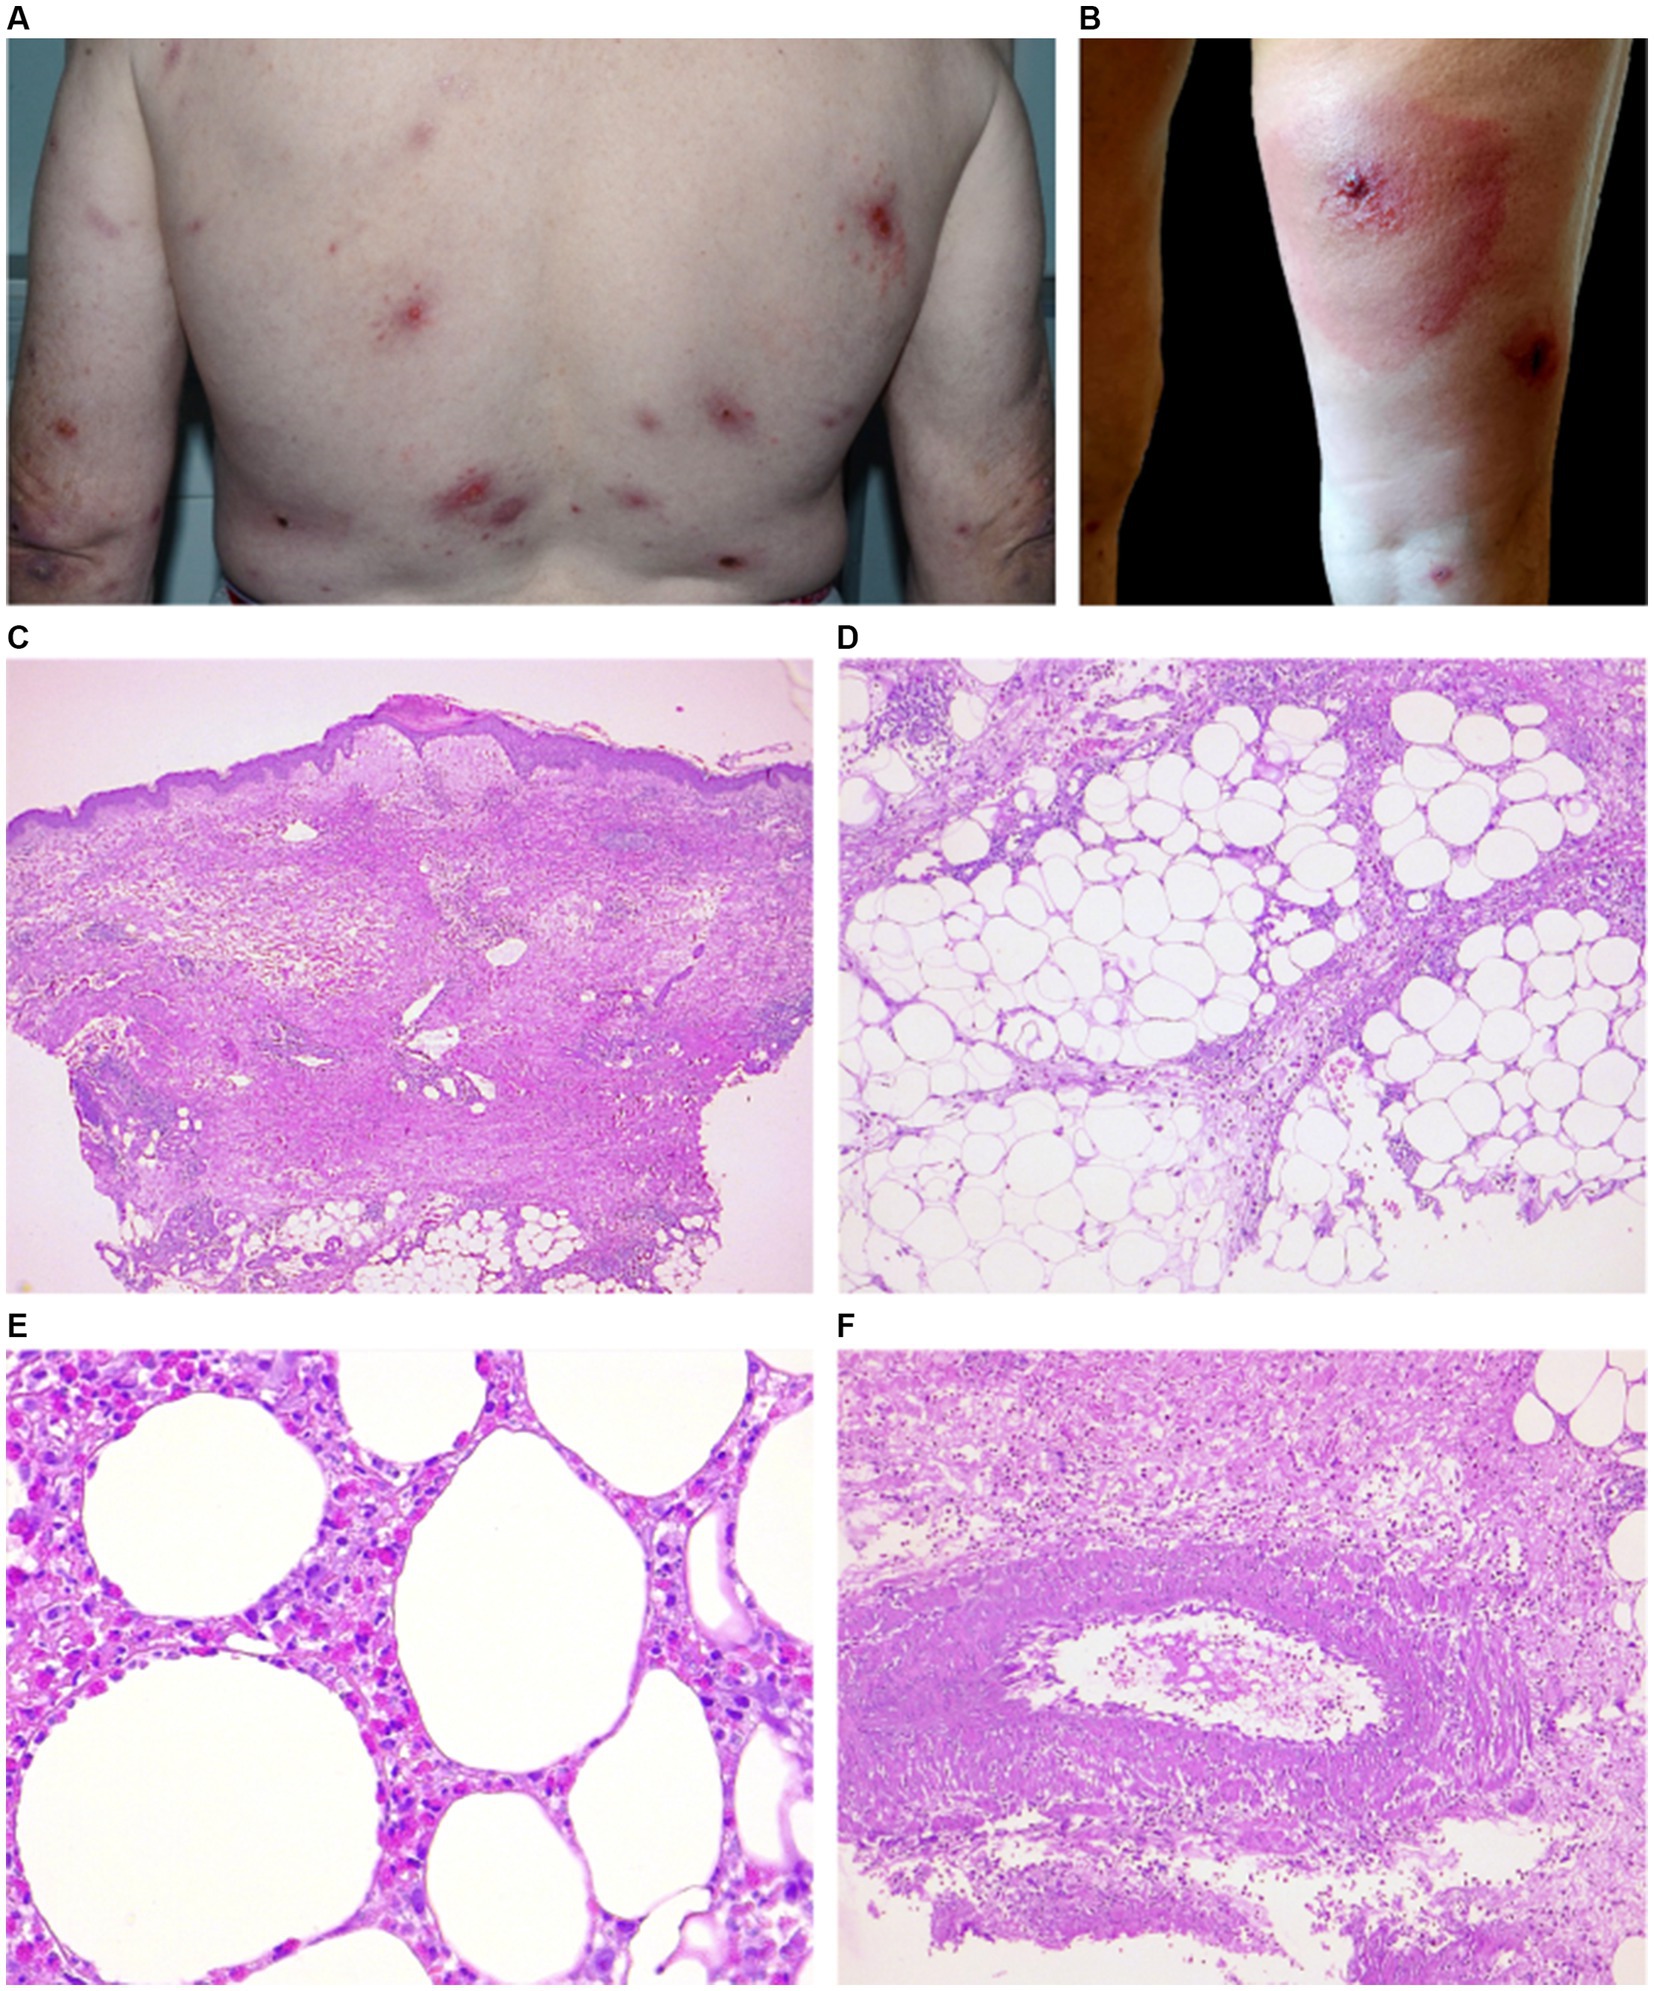

M551 EOSINOPHILIC CELLULITIS: A TREATMENT REFRACTORY CASE - Annals of Allergy, Asthma \u0026 Immunology

image size: 1668x1577

![Eosinophilic Cellulitis PDF] Flame figures associated with eosinophilic dermatosis of hematologic malignancy: is it possible to distinguish the condition from eosinophilic cellulitis in patients with hematoproliferative disease? | Semantic Scholar, image size:1200x672](https://figures.semanticscholar.org/6493287009fa9c164615e725d82a8c7c663c00b5/2-Figure1-1.png)

PDF] Flame figures associated with eosinophilic dermatosis of hematologic malignancy: is it possible to distinguish the condition from eosinophilic cellulitis in patients with hematoproliferative disease? | Semantic Scholar

image size: 1200x672